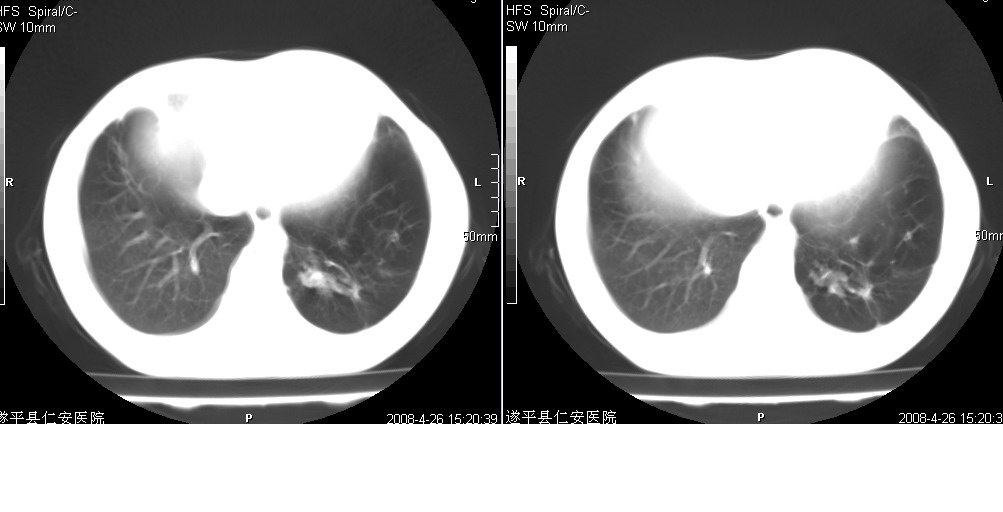

以下是引用yangyudong333在2008-4-27 16:58:00的发言:[br]病灶无明显分叶,周围有粗大索条影,外侧与胸膜接触面较宽且胸膜下透亮层存在,内部可见充气支气管,考虑炎症可能性大,建议抗炎治疗后复查

以下是引用mzh123在2008-4-27 19:30:00的发言:[br]右肺中叶团片致密影,周围可见卫星病灶,中叶支气管未见明显狭窄,所以首先考虑炎性病变,结核可能性大,肺癌待排,请治疗后复查!

以下是引用随光逐影在2008-4-27 20:49:00的发言:[br]考虑为:1)右肺中叶及左侧下叶感染性病变。2)左肺下叶支气管扩张?建议:抗炎治疗后复查。